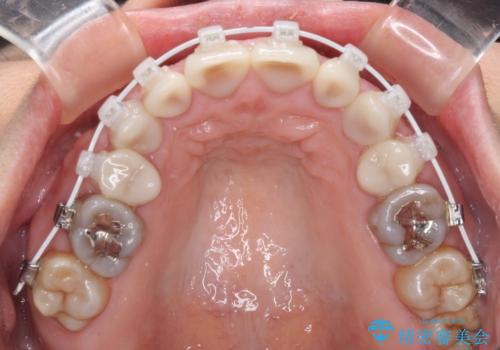

- 矯正装置

- 審美装置

- 小さいころからの歯の変色と矯正治療の後戻りを気にして来院された患者様です。

気になる変色歯を仮歯に変え、その後歯列不正を矯正治療で改善し、最後にオールセラミッククラウンにて補綴治療することとしました。